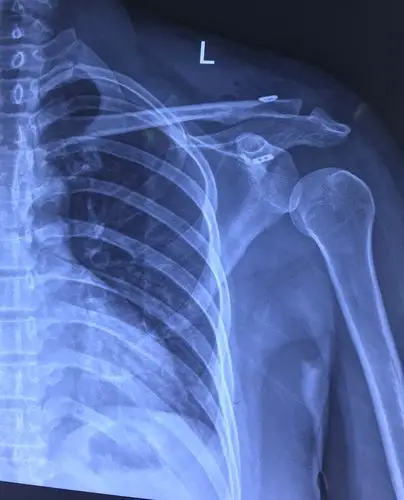

肩锁关节脱位

请问左肩锁关节脱位需要手术吗